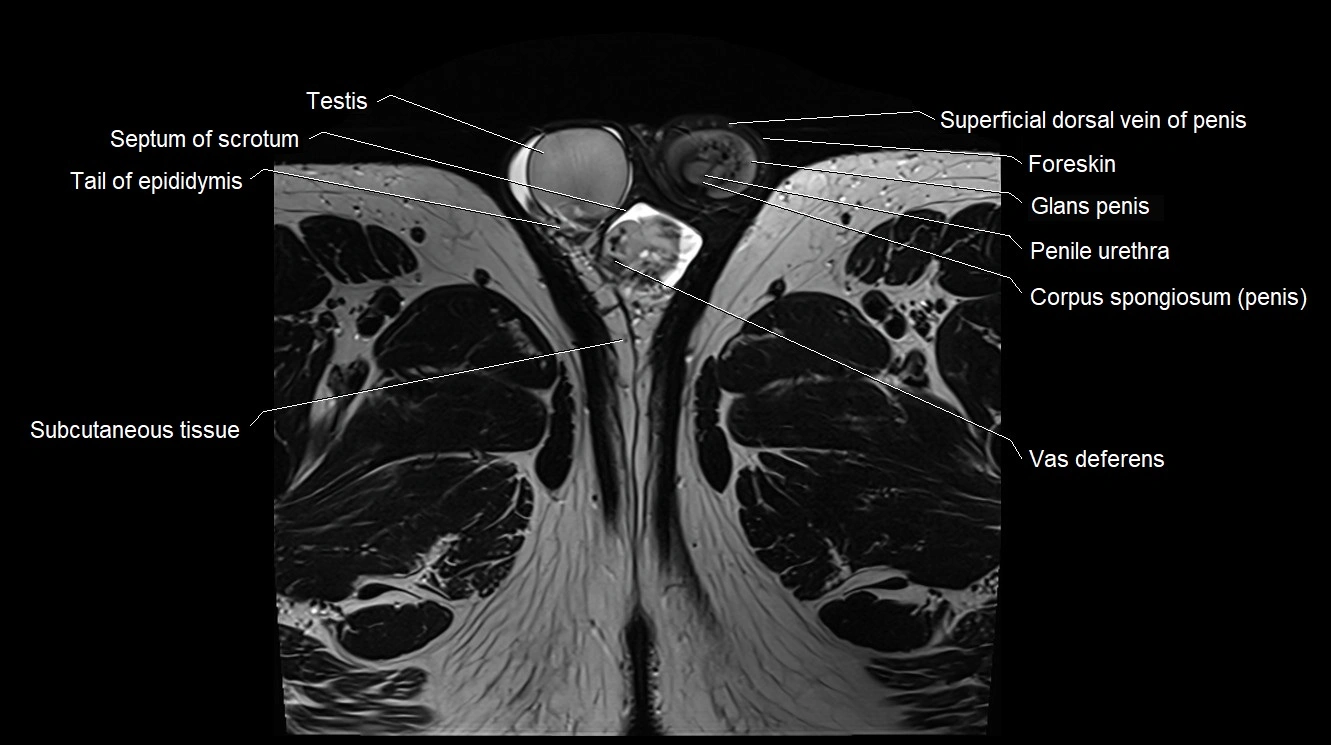

- Foreskin

- Glans penis

- Penile urethra

- Septum of scrotum

- Superficial dorsal vein of penis

- Tail of epididymis

- Testis

- Vas deferens